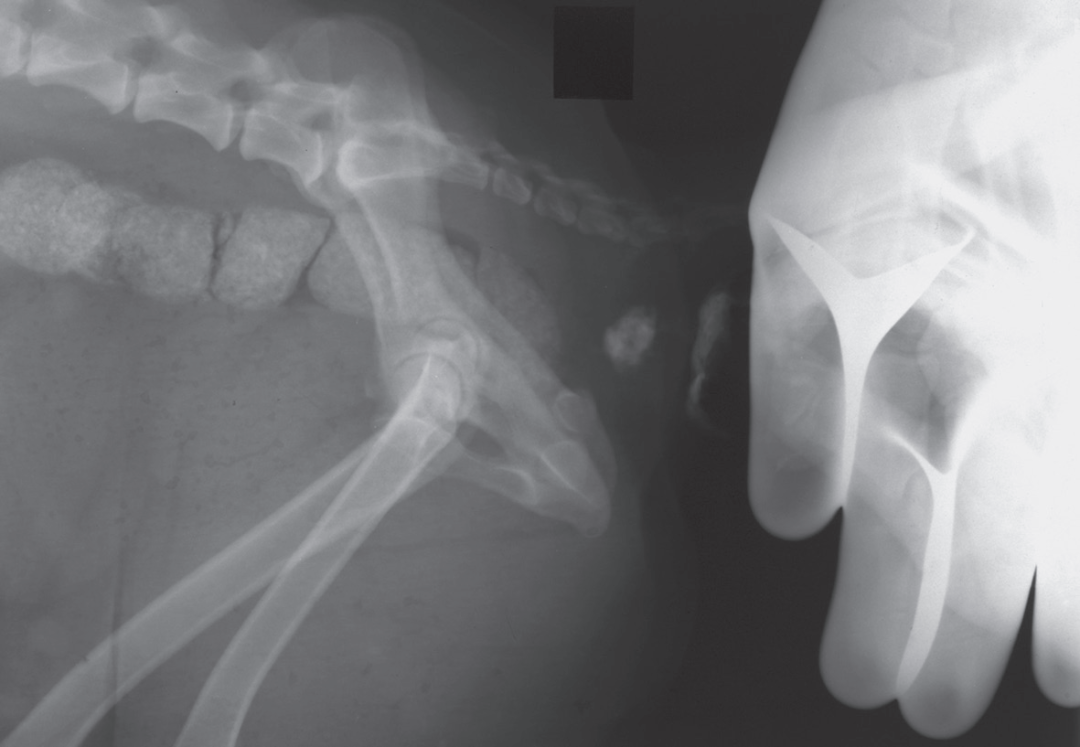

动物拍片腹部怎么摆小动物X线有哪2种辐射危害?辐射安全有哪3点原则?_https://www.jmylbn.com_新闻资讯_第4张

上图4.2——没有保护的人手出现在主光束中。这是完全不能接受的!因为动物摆位严重倾斜而且动物与人手互相重叠,这张X线片没有诊断意义。

动物拍片腹部怎么摆小动物X线有哪2种辐射危害?辐射安全有哪3点原则?_https://www.jmylbn.com_新闻资讯_第5张

上图4.3——检查者戴着铅手套出现在主光束照射范围内。放射技师穿着适当的防护服,然而,需要注意,这对主射线束没有保护作用!在铅手套的轮廓后面隐约可以看到检查者的手指。